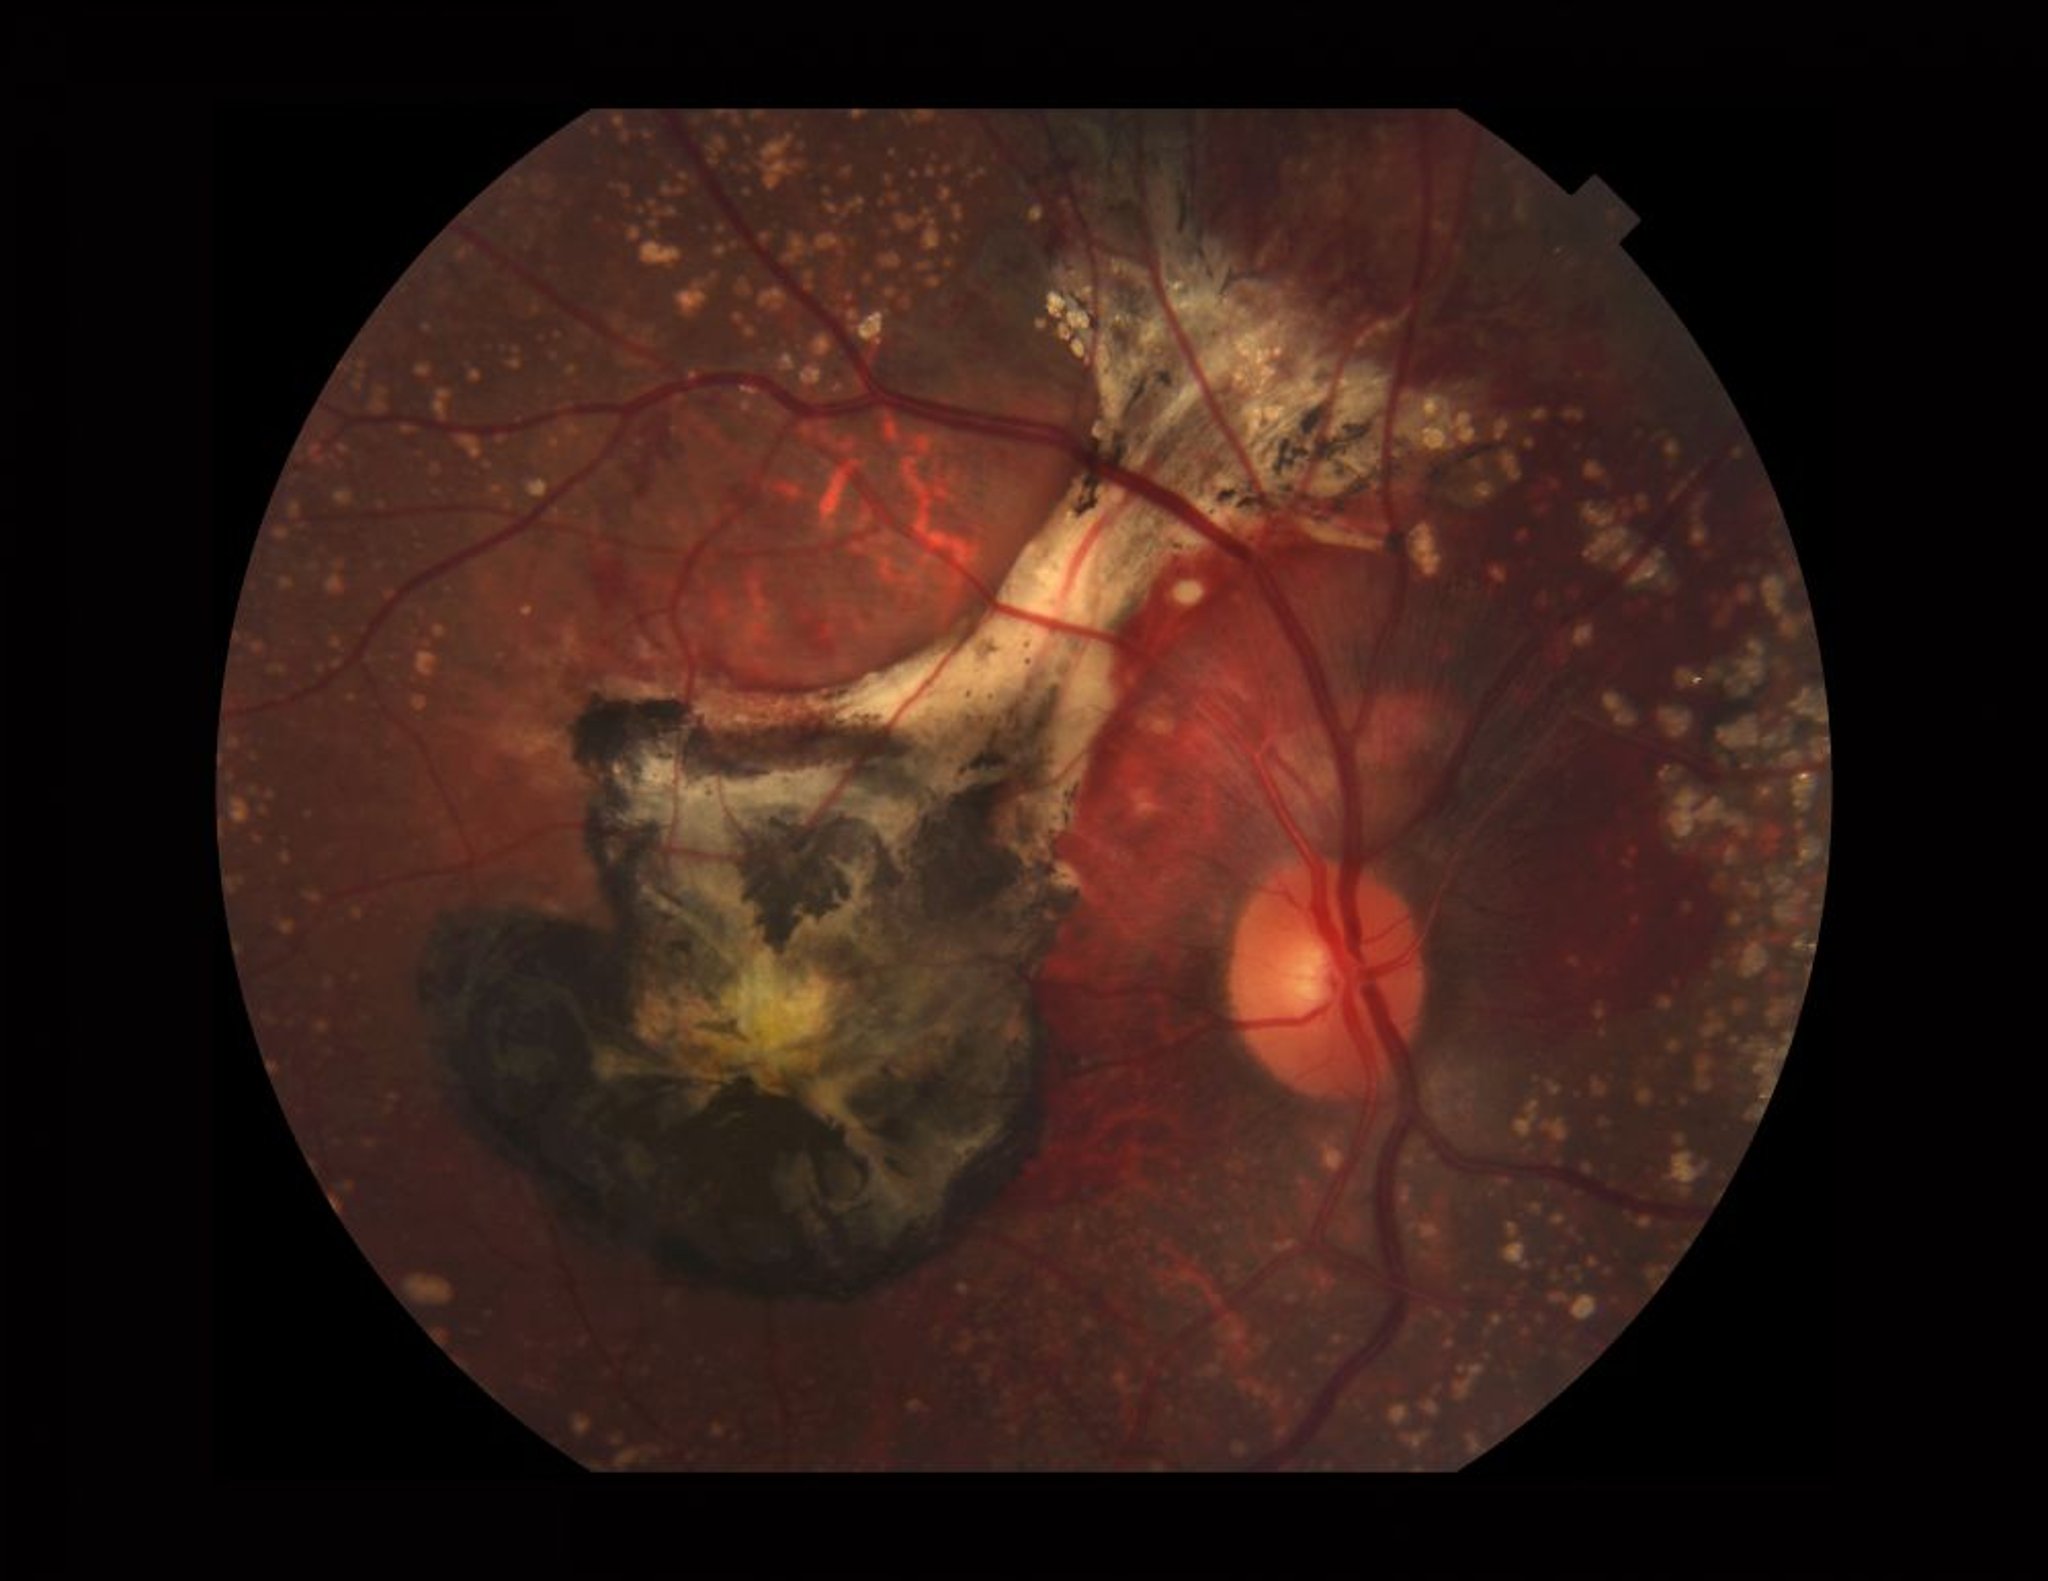

Degenerazione maculare legata all'età (forma umida)

Fotografia di una retina affetta da degenerazione maculare legata all'età umida (essudativa). Questa immagine mostra drusen calcificate, sanguinamento sottoretinico, una membrana neovascolare coroidale (nero da vecchio sangue e fibrosi) e pigmento di xantofilla (giallo) nella macula.